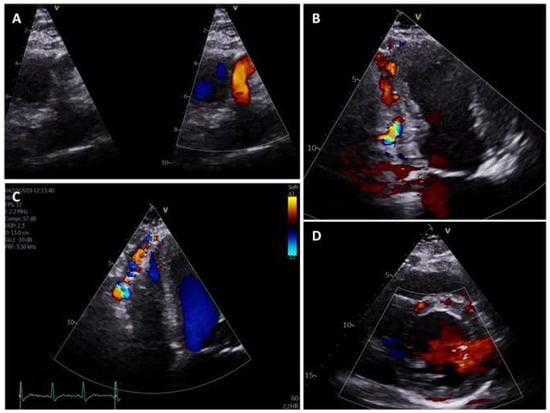

An outpatient transthoracic echocardiogram revealed moderate left ventricular dilatation (and mild dilatation of the right ventricle) with preserved systolic function, severe left atrial dilatation and moderate mitral regurgitation. Furthermore, an anomalous origin of the left coronary artery was also suspected because of the retrograde flow noted in the left anterior descending and left circumflex coronary arteries. A dilated right coronary artery and extensive collateral flow across the myocardium was also visualised (Figure 3).

Figure 3.

Transthoracic echocardiogram. (A): Modified parasternal long axis view showing a dilated right coronary artery to increase blood supply to the myocardium. (B): Modified apical 2-chamber view focused on the inferior wall showing prominent retrograde coronary flow from the septal perforator coronary arteries. (C): Modified apical 4-chamber view focused on the right ventricle lateral wall showing prominent retrograde coronary flow from the septal perforator coronary arteries extending towards the apex, also known as the “Christmas tree” appearance. (D): Parasternal short axis view at the level of the papillary muscles showing prominent retrograde coronary flow from the septal perforator coronary arteries.

Transthoracic echocardiography tends to be the first imaging modality in most clinical scenarios, and, as evident in our case, can be used to suspect ALCAPA. Some of the reported echocardiographic features of ALCAPA include [], mitral regurgitation, retrograde flow in the left coronary artery, dilated right coronary artery, collateral flow in the myocardium and an aberrant origin of the left main stem (Figure 3). This justifies the role of transthoracic echocardiography, a readily available and inexpensive tool that may uncover features of ALCAPA early on.